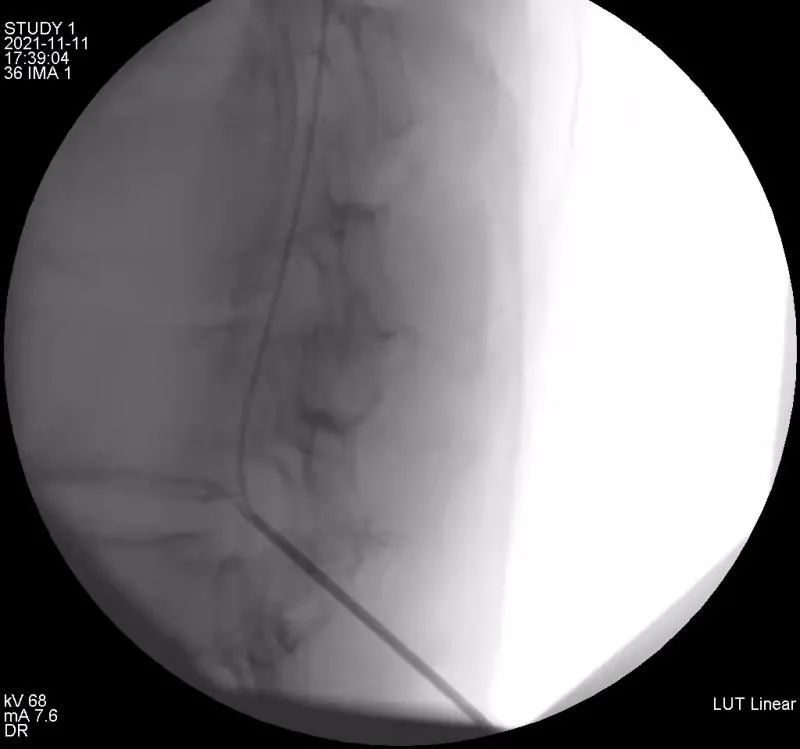

带大家了解下癌痛病人镇痛神器~鞘内吗啡泵

鞘内药物输注系统置入术――癌痛患者的福音(副本)

【病案现场】晚期癌痛治疗利器:鞘内镇痛泵植入术——同济大学附属

唐山市人民医院成功完成我市首例鞘内镇痛泵植入术